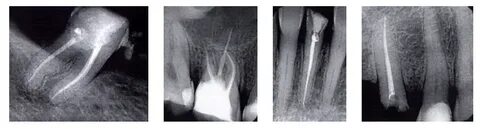

Рентгенопрозрачность: Гуттаперчевые штифты хорошо видны на рентгеновских снимках, что облегчает диагностику.

Процедура пломбирования

Процесс установки штифтов включает несколько этапов:

-

Очистка тканей: Удаляются кариесные наслоения и пораженные участки зуба.

Удаление пульпы: Пульпа зуба удаляется для предотвращения воспалительных процессов.

Обработка каналов: Увеличивается диаметр и размер каналов, производится дополнительная обработка антисептиками.

Установка штифтов: В каналы вводится специальная паста, после чего устанавливаются штифты - сначала основные, затем меньшие по диаметру. Это обеспечивает надежную фиксацию и поддержку для будущей реставрации.

Прессование: Выполняется прессование штифтов для достижения большей плотности и герметичности соединения.

Обрезка верхушек штифтов: После установки штифтов их верхушки обрезаются до необходимой длины, чтобы подготовить зуб к дальнейшей реставрации.

Закрытие зуба временной пломбой: На время до установки постоянной коронки зуб закрывается временной пломбой, что защищает его от внешних воздействий и инфекции.

Важно соблюдать все этапы процедуры с высокой степенью аккуратности, чтобы обеспечить качественную подготовку полости и сохранить естественную конфигурацию канала. Это критически важно для успешного результата лечения.